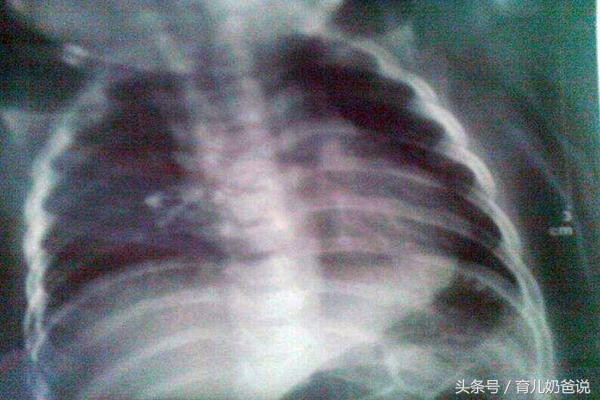

最近宝宝因为肺炎住院,在我们住院的第二天,进来一个哥哥,听他妈妈说昨天还好好的,今天医生叫拍片就确诊为肺炎了,但是看哥哥的精神状态,一点都不像患了肺炎的,除了有一点咳嗽之外并没有其他症状,妈妈因为害怕宝宝病情恶化,无奈的接受了住院。

哥哥在医院打了三天点滴,做了三天雾化后,情况有所好转,为了不让宝宝再打留置针(当时打留置针时用了三次才成功,宝宝哭得声音都快哑了),便问医生可不可以出院了,医生拿听筒听了听宝宝肺部,觉得还有一点喘便叫妈妈再带宝宝去拍一次片,确定肺部没问题就可以出院了,可是妈妈的反应很强烈,因为他觉得拍片对宝宝辐射太大了,不愿意几天内连续给宝宝拍两次,最后医生给她做了详细的解释才妥协。

医院儿科平时常见的检查有B超、磁共振成像、x光摄片和CT。其中B超和磁共振成像完全没有辐射,如果医生要求宝宝做这两项检查,完全可以放心去做。x光摄片和CT依靠的射线成像,存在一定的电离辐射,其中CT辐射量相比x光摄片可能要高出十倍、四十倍,甚至是上百倍,但是其清晰度和精准度都比x光摄片要高得多。平时宝宝肺炎医生所说的拍片基本都是x光摄片,如果宝宝肺炎久治不愈,严重到出现并发症,不得已时医生才会让孩子进一步做CT。